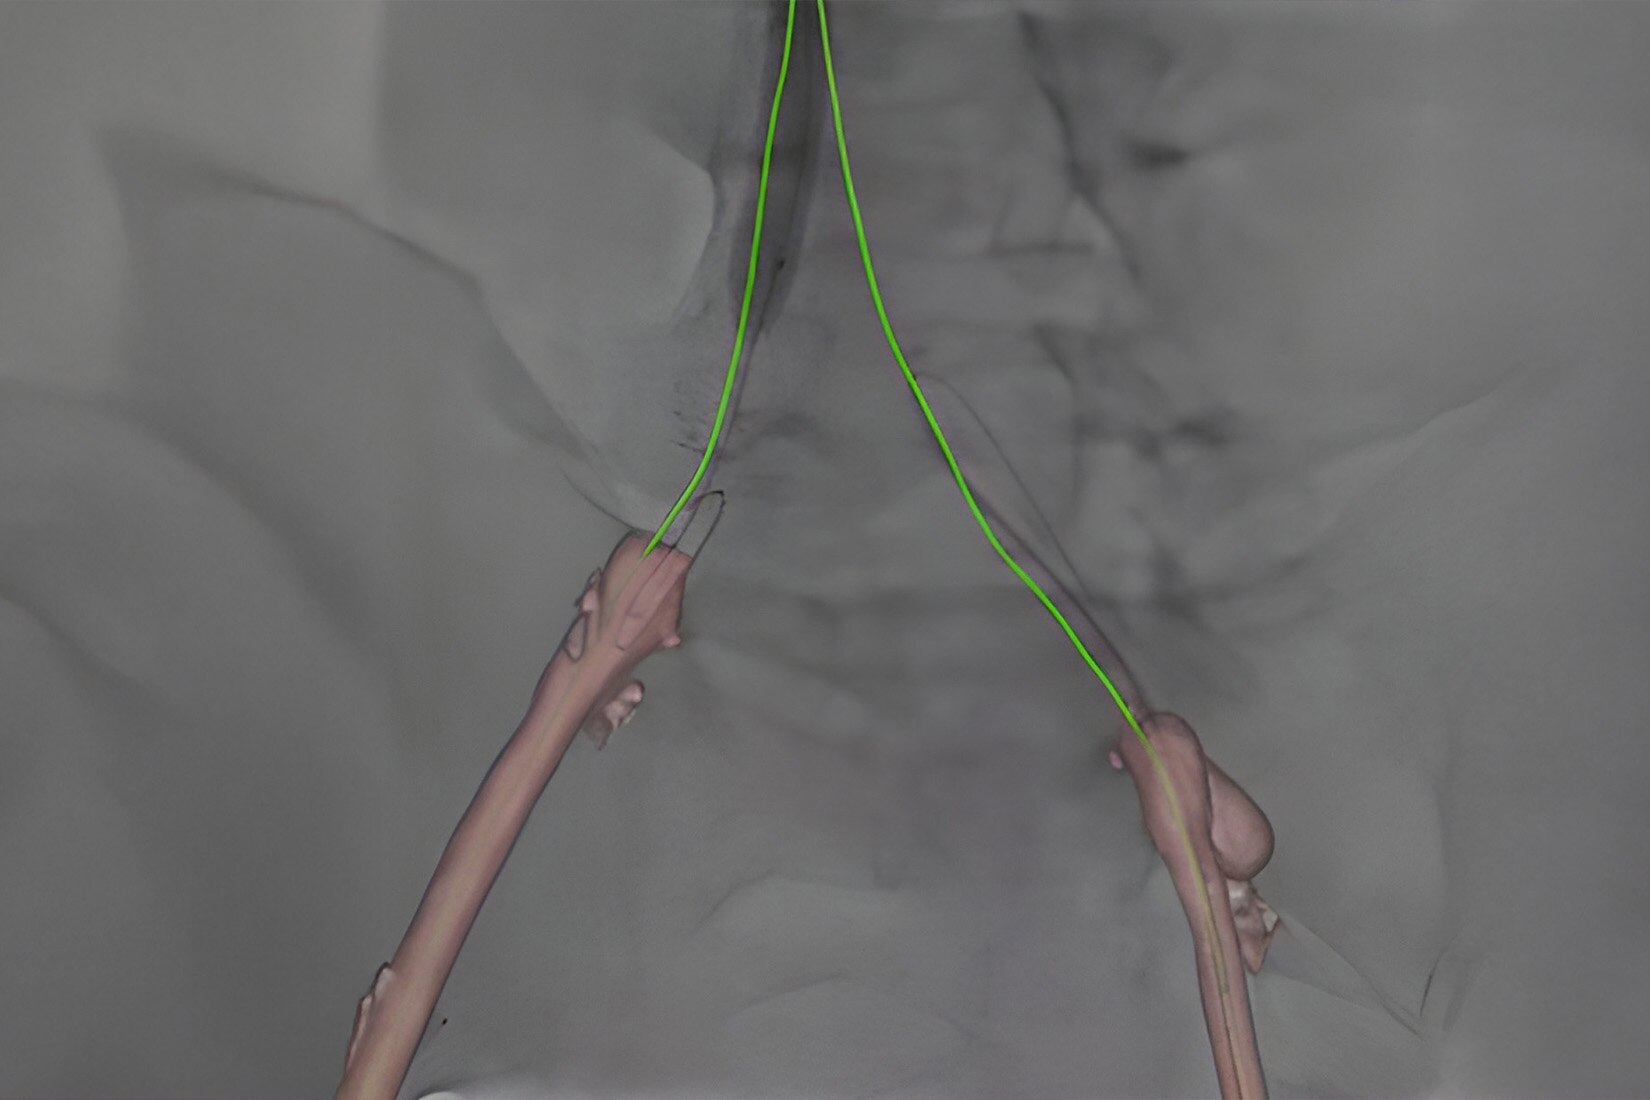

Vessel assist for neurointerventional

Vessel ASSIST delivers accurate and easy anatomy segmentation and accurate vessel quantification from 3D volumes. It also offers advanced 3D roadmap and augmented image guidance capabilities on frontal or lateral planes to guide catheter with confidence for procedure such as Aneurysm Treatment with Flow Diverter.

Plan

Segment and size the anatomy of interest in CBCT.1 Plan the stent positioning on the 3D model and prepare 3D landmarks to help guide the deployment.

Import segmented anatomy, centerline and landmarks and overlay them on live fluoroscopy on the frontal or lateral plane for 3D fusion guidance.